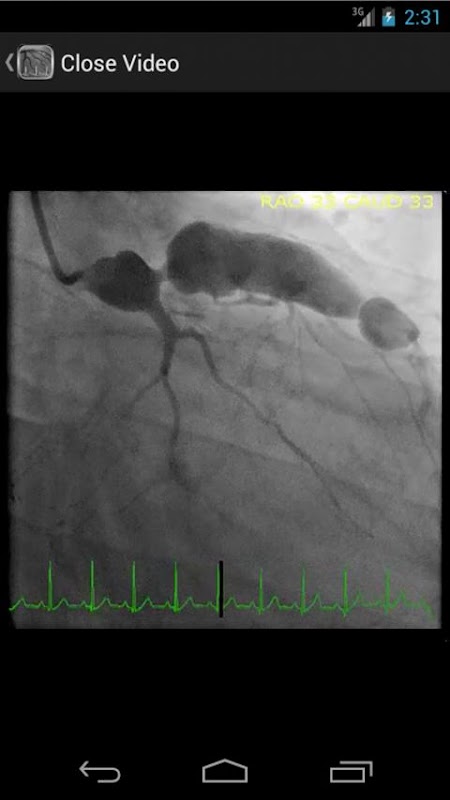

* Bazę danych zawierającą ponad 30 filmów (angiografii wieńcowej, ventriculograms i aortograms) obu wspólnych i rzadkich ustaleń w pracowni cewnikowania serca

CathSource zapewnia szczegółowy przegląd najważniejszych cewnikowania serca i angiografii tematów, zawierające edukacyjne obrazy / wideo, a także opinie o stosownej literaturze medycznej. CathSource jest idealnym rozwiązaniem, aby pomóc w zrozumieniu i rozpoznawaniu patologii układu krążenia w laboratorium cewnikowania.